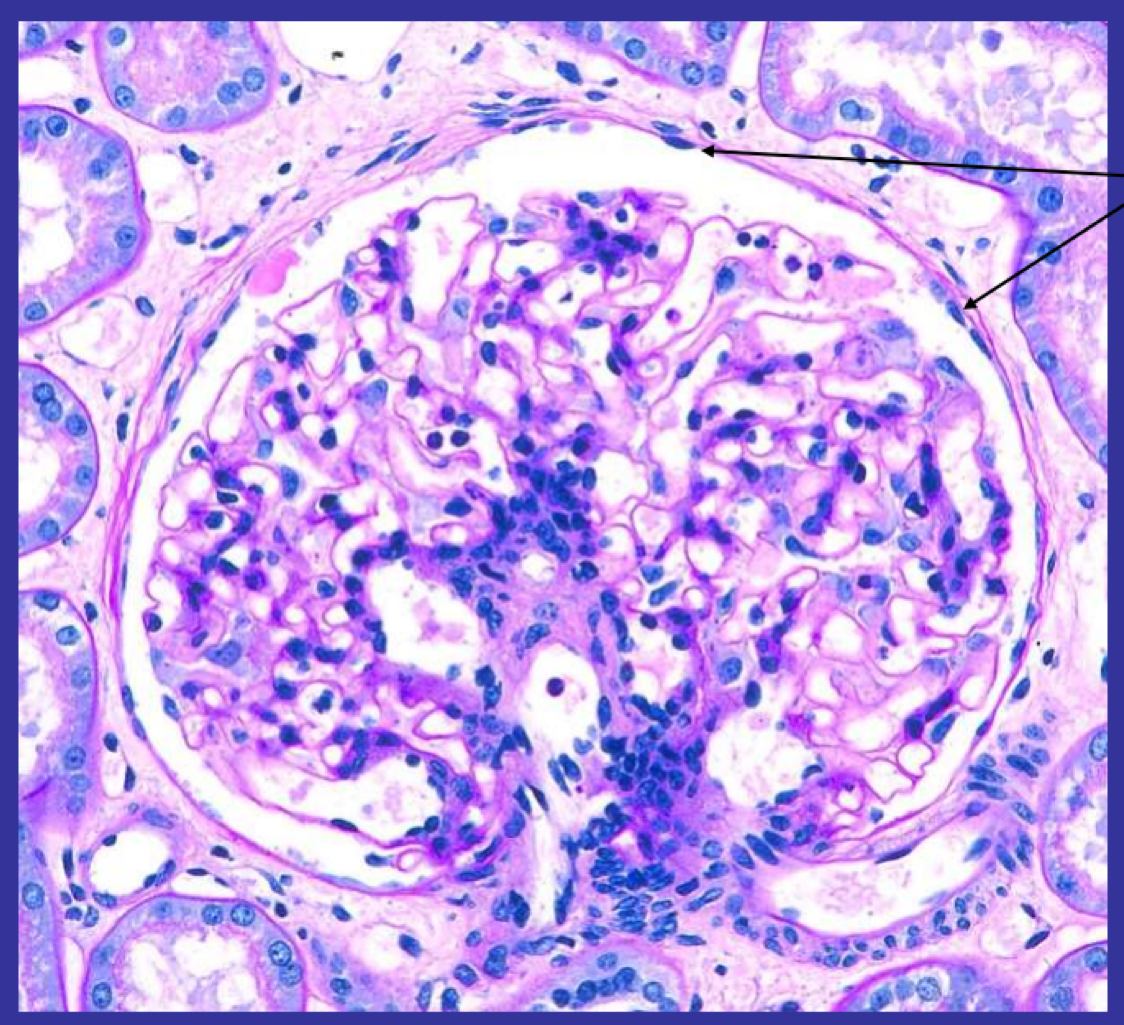

Wht structure is this and where is it found?

Glomerulus found in the kidney